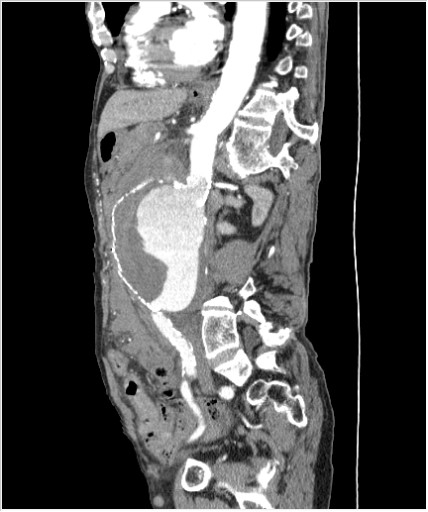

КТ брюшной полости. Мужчина с пальпируемой опухолью в животе

Пациент Т. 64 года, обратился на КТ брюшной полости амбулаторно (!), по направлению семейного врача с диагнозом abdominal mass, буквально: образование брюшной полости.